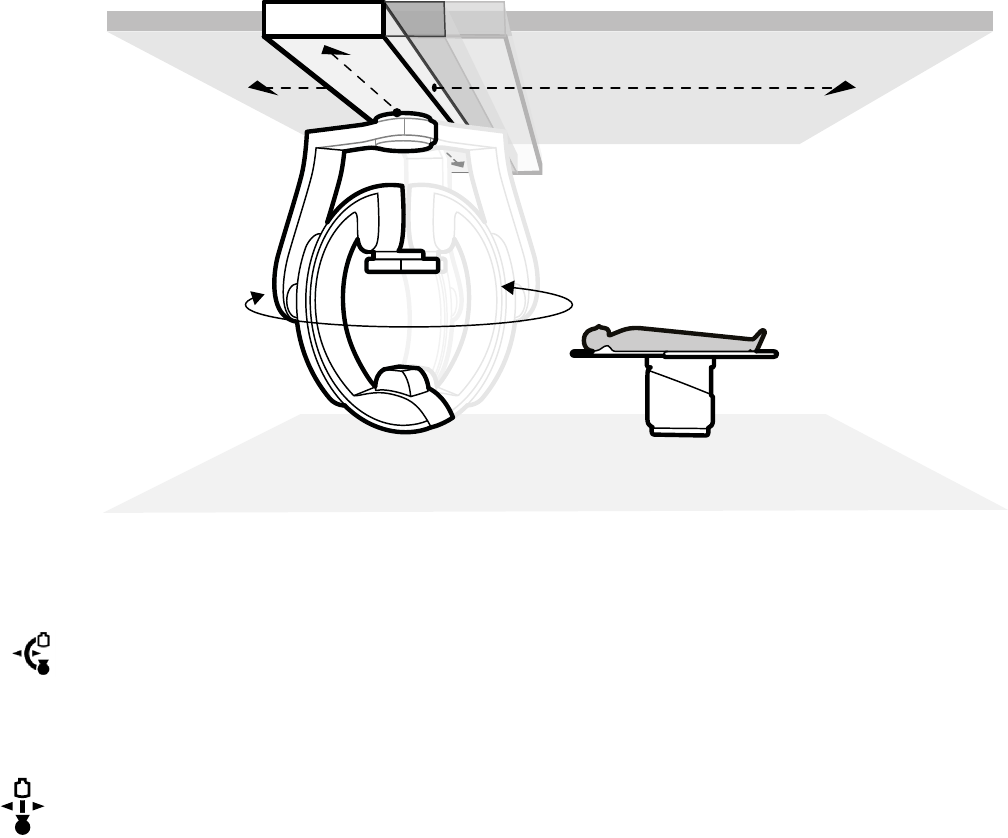

5.9.2 Ustawianie ramienia C........................................................................................... 55

5.9.3 FlexMove................................................................................................................56